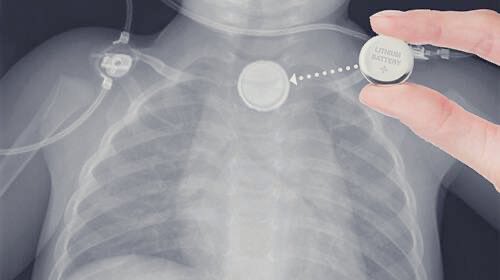

🔰من المهم جداً ان نتطرق الى مخاطر البطاريات :

معظم حالات ابتلاع البطاريات تكون خطيرة .هناك حالات أدّت للوفاة أو لحدوث حرق أو ثقب في المريء أو القصبة الهوائية مصحوباً بمضاعفات خطيرة ، كالحاجة لتدخل جراحي

هذه المضاعفات تحدث عندما تعلق البطارية في المريء ولا يتم إزالتها خلال ساعتين ، حيث تشكل ما يشبه السائل الكاوي الذي يتسبب في تسمم الأطفال . وضع البطارية في الأنف أو الأذن يعدّ أيضاً أمراً خطراً ويستدعي إزالة البطارية في أسرع وقت .